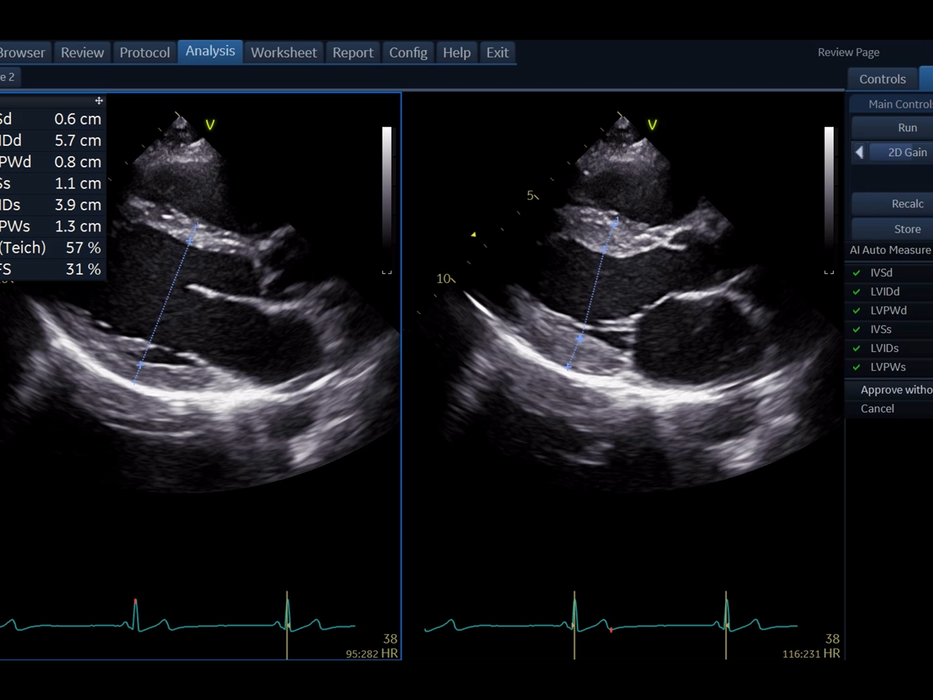

AI Auto Measure

Přesné měření s AI Auto Measure

Technologie AI Auto Measure v systému Vivid T9 umožňuje rychlé a přesné měření s minimálním manuálním zásahem. Tento nástroj zajišťuje vysokou reprodukovatelnost výsledků a zefektivňuje pracovní postup.